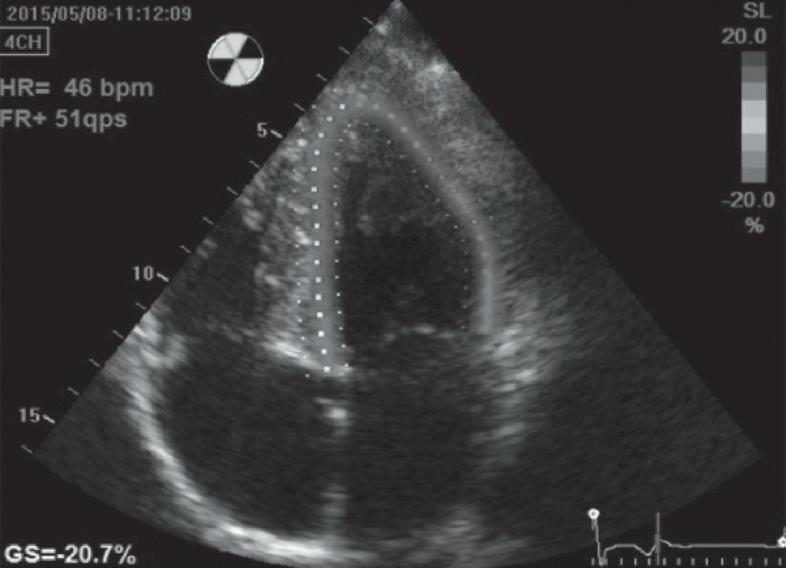

18 O Ecocardiograma no Manejo do Paciente Crítico, 193 Rodrigo Ferraz Salomão • Flávia Guimarães Brasil • Eduardo Boetner